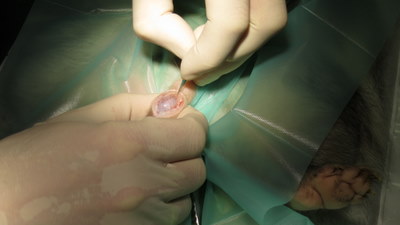

Het scrotum wordt ingesneden

Het testikel komt tevoorschijn

Het testikel en de bijbal worden losgeprepareerd van het scrotum

De testikel wordt afgebonden